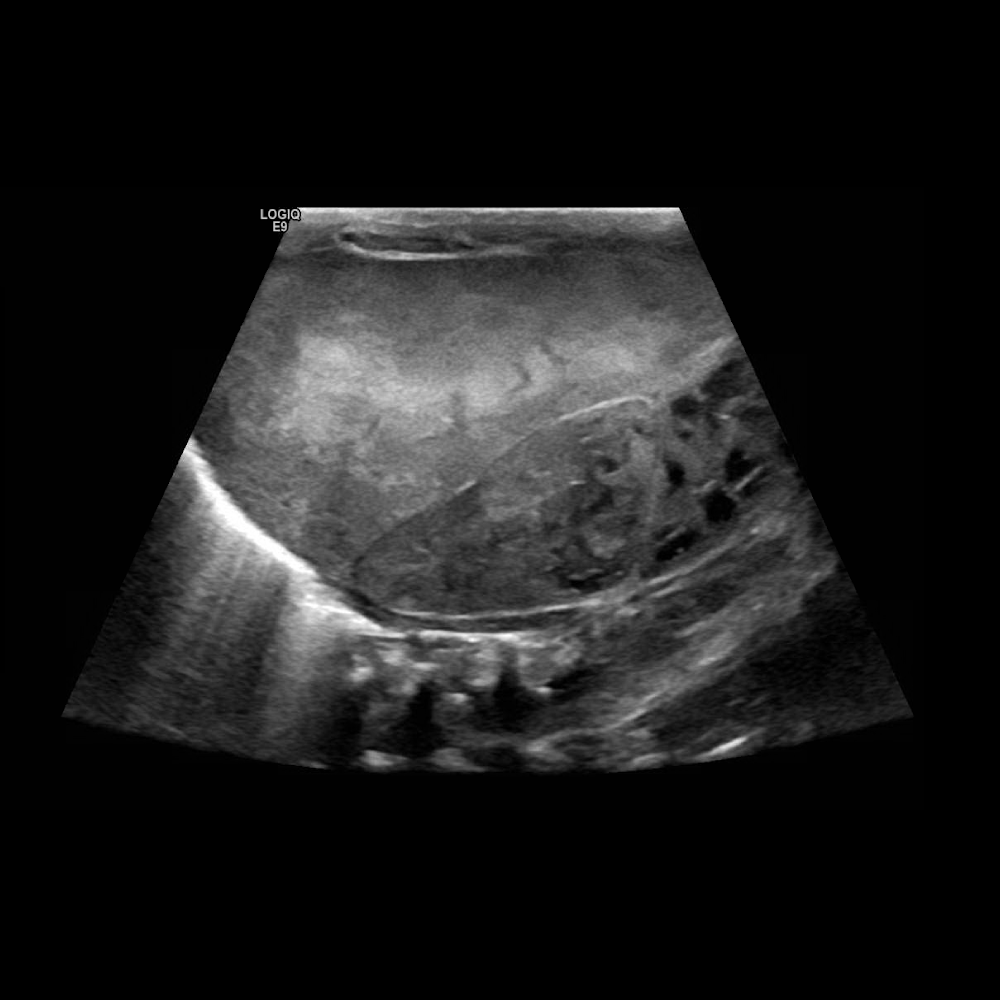

Right adrenal Neuroblastoma with metastasis to the liver.

Retroperitoneal Neuroblastoma causing biliary obstruction.